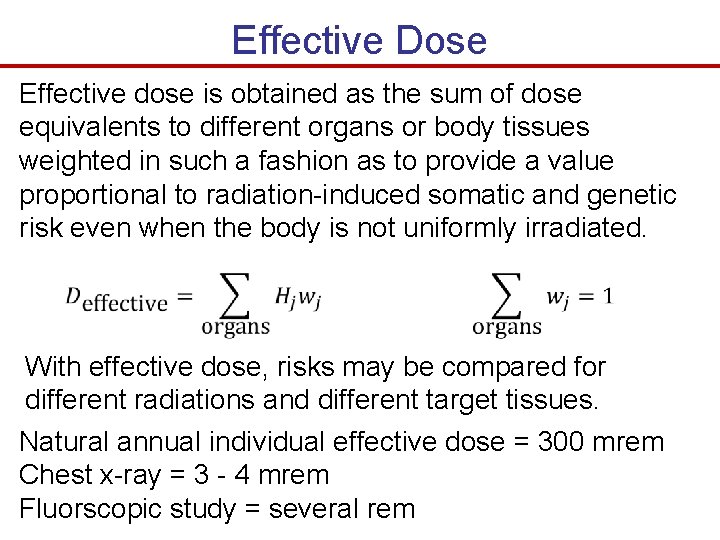

Effective Dose Effective dose is obtained as the sum of dose equivalents to different organs or body tissues weighted in such a fashion as to provide a value proportional to radiation-induced somatic and genetic risk even when the body is not uniformly irradiated. With effective dose, risks may be compared for different radiations and different target tissues. Natural annual individual effective dose = 300 mrem Chest x-ray = 3 - 4 mrem Fluorscopic study = several rem